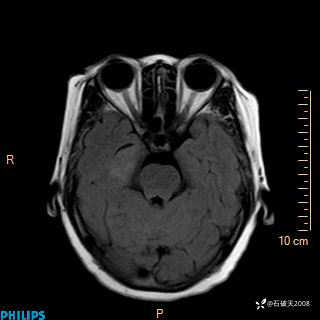

颅内占位,影像征象不是很丰富,有病理

hyy838 推荐女 62岁 主 诉:头晕12小时,加重1小时。

现病史:患者于12小时前无明显诱因出现头晕,呈持续性,无天旋地转及行走不稳,伴恶心、呕吐,呕吐共5次,呕吐物为胃内容物(具体性质不详),无胸闷、胸痛、心慌,无腹痛、腹泻,无咳嗽、咳痰,无发热、意识不清、肢体抽搐及大小便失禁等,1小时前患者上述症状加重,未诊疗,为求进一步治疗急自行来我院,门诊以“头晕待查”为诊断收入我科,发病来,神志清,精神差,饮食、睡眠差,大小便正常,体重未见明显下降。

T2